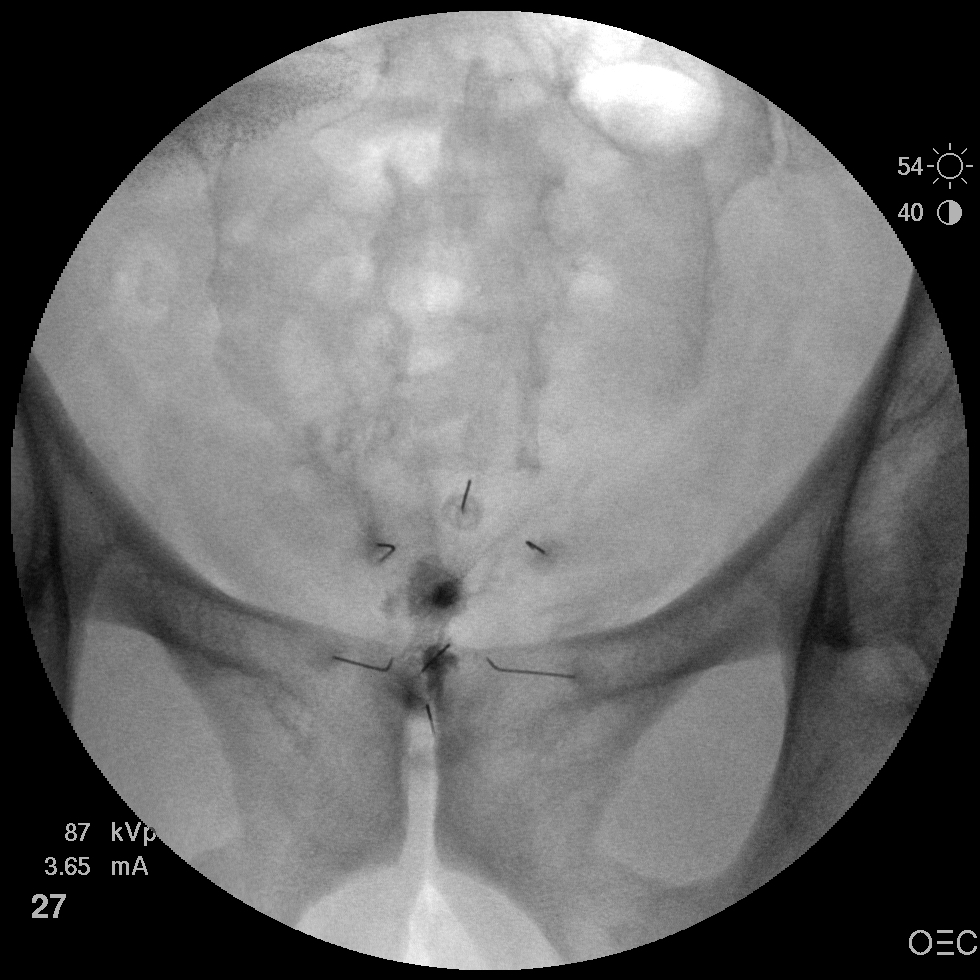

I have a patient with several months of coccyx pain. Worse with sitting, TTP over coccyx. Otherwise normal exam. No trauma, but she has an anteriorly displaced coccyx. Failed NSAIDs and no one around me does good pelvic floor PT. I scheduled her for ganglion impar injection, but her insurance won't pay for it. They wouldn't even let me to a peer-to-peer... they just straight up said they won't cover it. Any other treatment options? I don't want to send her to a surgeon. Thanks.